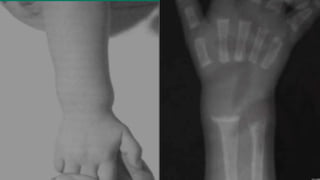

Дівчинка 4 років. Діагноз

– вітамін Д-залежний

рахіт.

Варусно – саблеподібна

деформація нижніх

кінцівок, деформація

черепа та грудної клітки,

рахітичні “браслети”